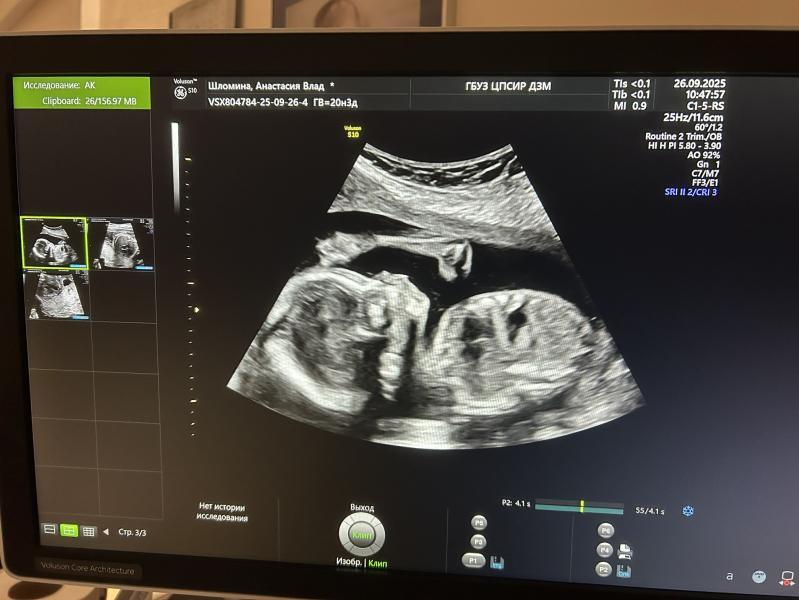

Повидались с нашей Агушей🥰

370гр счастья)